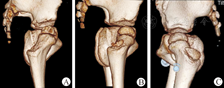

1936年,Kleinberg和Lieberman最早提出了髋臼指数概念作为髋关节脱位的影像学诊断指标[9]。目前,髋臼指数已广泛应用于婴幼儿髋关节发育的影像学评估[10],对于髋臼发育不良和髋脱位后残余髋臼发育不良的患儿,髋臼指数可以预测其是否需要接受骨盆截骨术,有助于临床医生对其治疗方案的选择和制定[11,12]。虽然已被广泛应用,但是其测量的准确性仍然受多种因素的影响,骨盆的摆放体位[13,14],髋臼外上缘骨性部位的选择,H线选择不同等均是髋臼指数测量差异的主要来源。临床上,不同医师基于同一张骨盆X线平片所测得的髋臼指数也可以存在很大差异。因此,选择正确的髋臼外上缘将会使所测的髋臼指数更加接近于"真实"值。通过骨盆三维CT数据进行骨盆模型重建,生成的DRR图像能够代替该骨盆空间位置下X线光照射所生成的骨盆平片,其有效性和准确度已经得到了广泛的认可[15]。前人的研究显示儿童髋臼指数的测量误差约在3°以内[13],而本研究中所有髋关节采用A点和B点测量的髋臼指数差值为(3.06±3.06)°,其中Ⅳ型髋臼的测量差值为(7.22±2.25)°,最大达到11.60°,远远超过了AI的测量误差。Kim等[16]也选取不同的髋臼外上缘点进行髋臼指数同样也发现此差异,但其研究并未验证两种方法测量值与真实值的差异。Agus等[17]采取上述两点测量中心边缘角探究其合理测量方法,发现其两种测量方法的差异在3.6°左右。我们的研究,排除了骨盆异常体位所带来的误差,在标准的骨盆空间位置上,可以同时获取类骨盆平片的DRR图像和准确反映骨性髋臼外上缘的冠状位CT图像,该方法不但能够观察两种测量方法的差异,并且为不同的髋臼指数与"真实"髋臼指数的直接对比提供了条件。本研究中,按照Ogata等[7]的髋臼形态分型方法,我们看到Ⅰ/Ⅱ型髋关节因其A点与B点重合,故该类髋关节其AAI与BAI差值为零;Ⅲ型髋关节其差值为(3.77±1.78)°,而Ⅳ型髋关节差异值则达到(7.22±2.25)°,其三者差异具有统计学意义。此外,正常髋关节的AAI与BAI差值较发育不良髋关节的差值较小,然而其差异并没有统计学意义。可见,骨盆X线平片上髋臼外上缘的形态改变是决定AAI与BAI差异大小的关键,这意味着,对于Ⅳ型髋关节而言,髋臼外上缘测量参照点的错误选择将对AI测量产生巨大的影响。临床上,髋臼指数反映的是髋臼顶部对股骨头的骨性覆盖。本研究中,我们选取通过该侧股骨头最大直径的骨盆冠状位MPR片,此时的骨性髋臼代表髋关节中心平面的髋臼顶,该平面上测量CTAI所采用的外上缘点即为真实的髋臼骨性外上缘点,因此,我们认为其能代表"真实"的髋臼指数。根据本研究结果,CTAI与AAI之间具有极高的相关性并且两者之间差异并不明显,Bland-Altman分析显示其两者具有高度的一致性。根据统计学原理,AAI与CTAI的测量结果在一定程度下可以互换,A点在骨盆平片上相对于B点能够更加准确的反映真实的髋臼外上缘点。然而,本研究结果中,仍然存在3例髋关节其CTAI与AAI的差异过大。对该3例髋关节进行骨性三维重建,我们发现该3例病例的髋臼病理改变均为局部的髋臼中上缘缺损型(图6)。本研究测量的CTAI在髋关节中心冠状位平面上进行测量,当MRP平面通过髋臼中上缘骨性缺损时,在CT图像上测量髋臼指数时其外上缘的终点将会向内侧移动,该情况导致CTAI的值增大,而此时在骨盆平片上,髋臼上缘其余部分未出现缺损,因此A点并未产生移动,此时AAI的测量值所反映的仍然是真实的骨性髋臼覆盖。髋臼缘局部的病理变化导致CTAI与AAI的差异增大,其散点分布在两者平均差异的95%可信区间之外,影响了整个研究数据的一致性。

最后纳入研究对象总共33例,年龄为(2.90±1.32)岁;其中男8例,女25例,共52髋;影像学上按照Ogata髋臼形态分型,Ⅰ/Ⅱ型共19髋,Ⅲ型23髋,Ⅳ型10髋。按照髋关节发育不良的诊断标准[8],其中26髋为正常髋关节,26髋为发育不良髋关节。对于所有髋关节,其CTAI的测量值为(28.40± 6.74)°,AAI的值为(27.98±6.51)°,而BAI的值为(24.93±5.62)°,AAI与BAI的差值为(3.06±3.06)°,范围为0~11.60°。表1显示AAI与BAI的差值在正常组髋关节与发育不良组髋关节之间差异无统计学意义(P=0.181),而在影像学分型中,各组间差异具有统计学意义(P<0.001);可见AAI与BAI的差异受到髋臼外上缘显影形态的影响,而不受髋臼发育状态的影响。CTAI与AAI之间呈高度相关(P<0.001),其两者差异未见明显统计学意义(P=0.112),CTAI与BAI之间也呈高度相关,其两者之间差异具有统计学意义(P=0.000,表2)。CTAI与AAI之间的差值为(-0.41±1.83)°。采用Bland-Altman分析检验CTAI与AAI测量的一致性,图5显示大部分的髋关节其CTAI与AAI的差值均位于其平均差值的95%可信区间以内,而有3髋其CTAI值与AAI值差异与其余髋关节相比增大,导致散点分布在CTAI与AAI平均差异的95%可信区间以外范围(图5)。